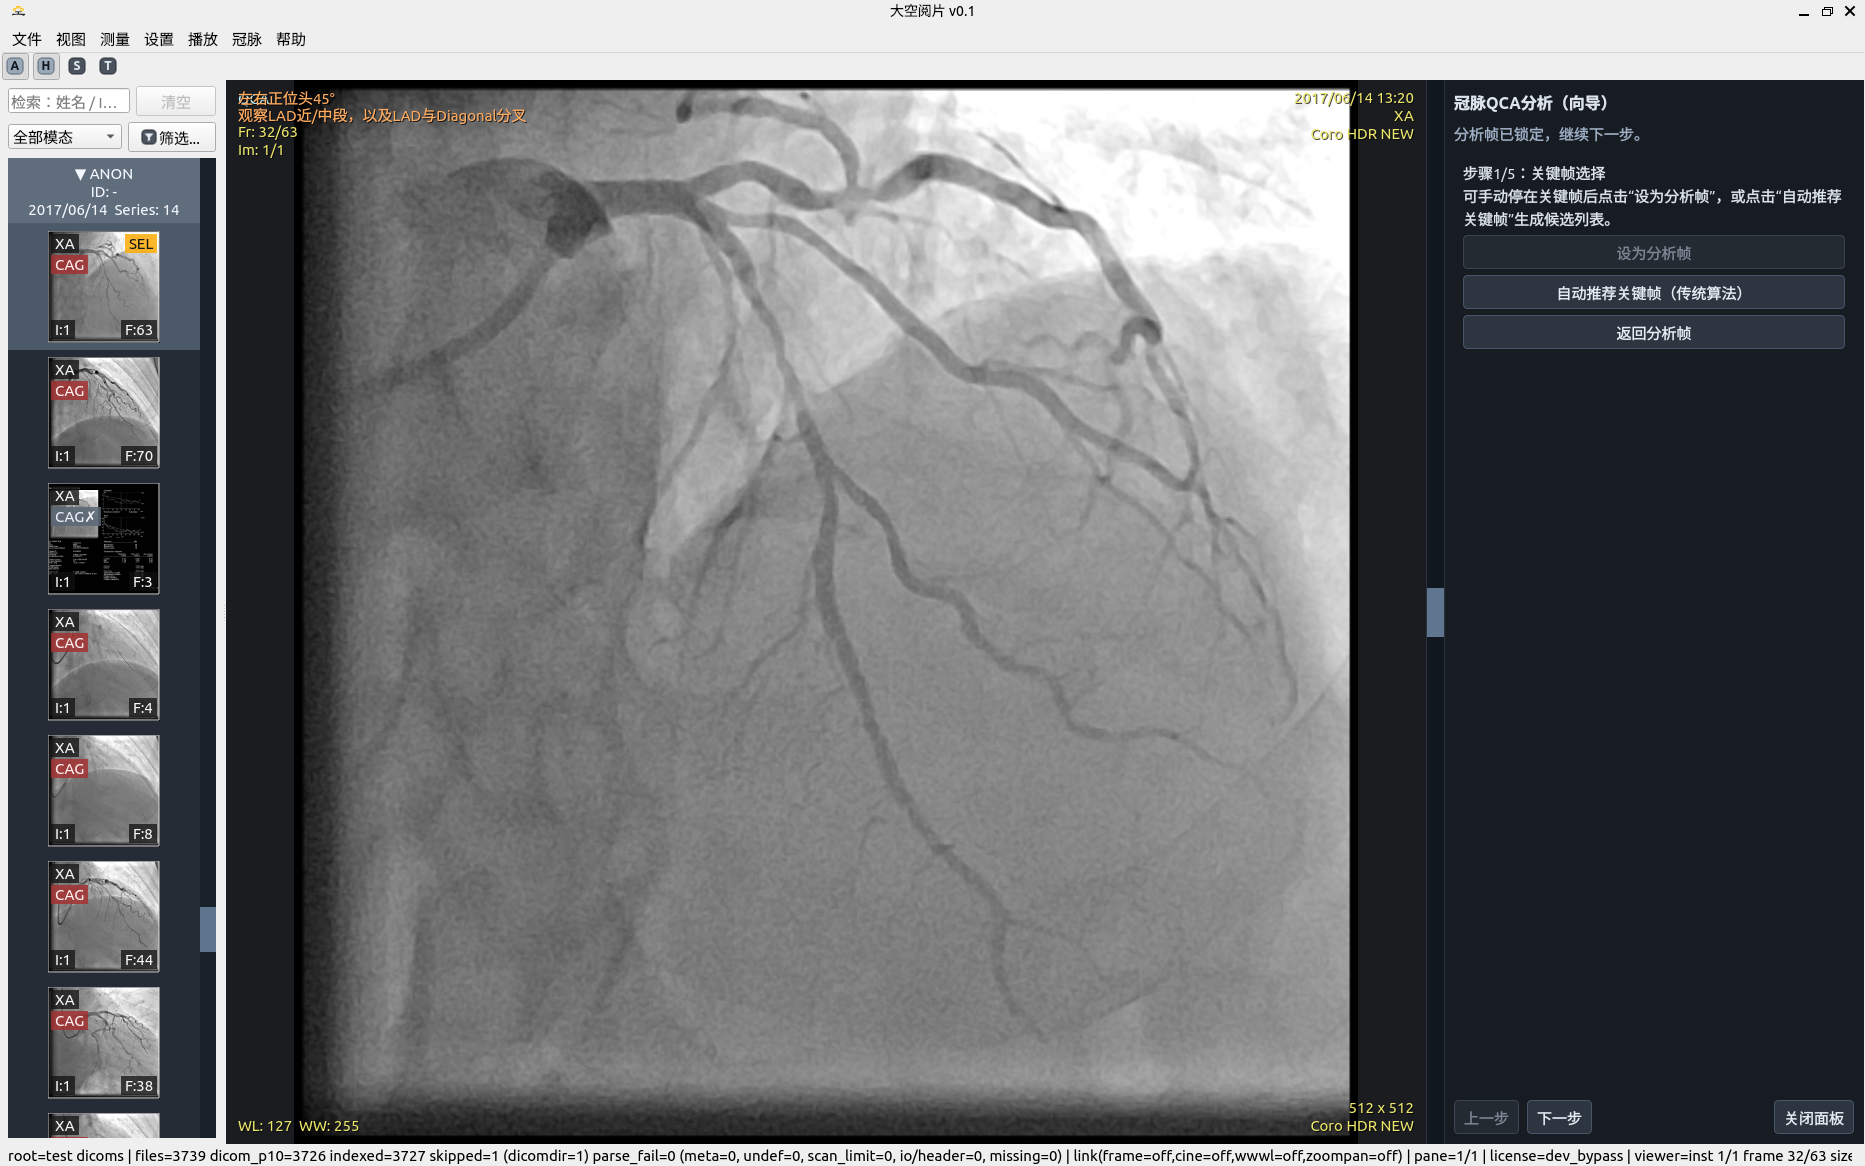

QCA 分析步骤 1

关键帧选取